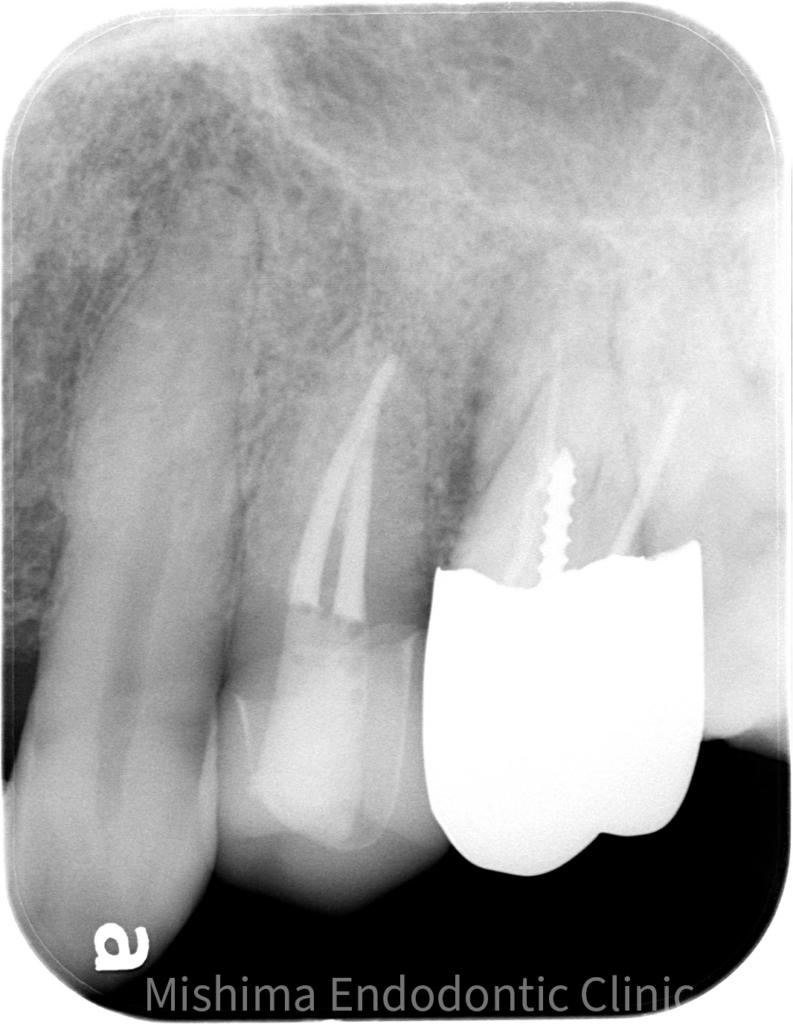

After

| 治療内容 | 23が既に根管治療が介入され仮封の状態で、サイナストラクト、自発痛を認めた。 根管治療を行うも症状の改善認めず、歯根端切除術へ移行。 |

| 治療期間・治療回数 | 3回 / 1ヶ月 |

| 治療費用 | 根管治療 121,000円 隔壁 5,500円 支台築造(ファイバー) 16,500円 歯根端切除術 99,000円 |